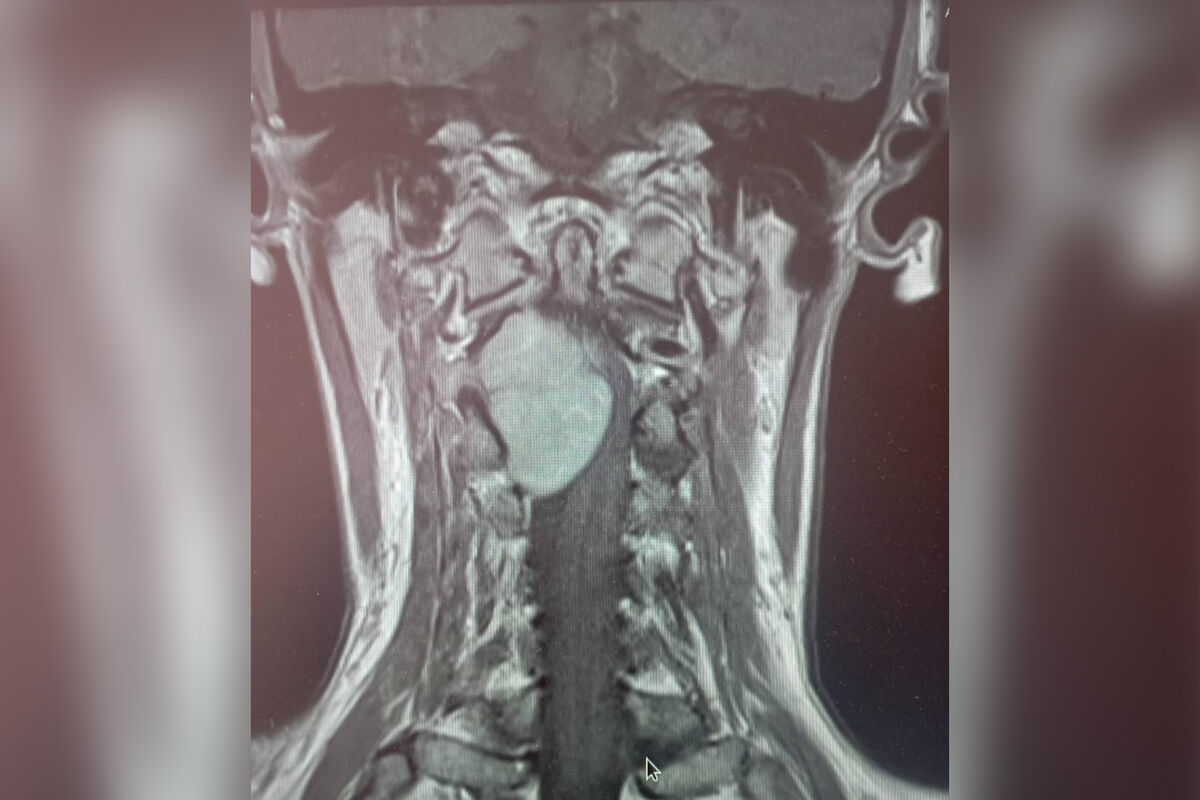

У россиянки с онемением руки и ноги нашли огромную опухоль в шее

В Липецке у женщины с отнимающимися рукой и ногой нашли опухоль в шее

Врачи больницы скорой помощи Липецка прооперировали 35-летнюю женщину с огромной опухолью в шейном отделе позвоночника. Об этом региональный министр здравоохранения Анна Маркова сообщила в своем Telegram-канале.

Пациентка обратилась к медикам с жалобами на отнимающиеся руки и ноги. МРТ показало, что проблема кроется в шейном отделе позвоночника, где выросло большое новообразование.

«Шейный отдел — очень опасная локализация. Спинной мозг здесь переходит в головной, кроме того, в шее проходит большая нервно-сосудистая магистраль. Опухоль в этом отделе представляет серьезную угрозу и может привести к парализации», — рассказал нейрохирург больницы Леонид Осолодченко.

Медики приняли решение оперировать пациентку. Вмешательство длилось около пяти часов и прошло успешно. Через десять дней женщину выписали домой. Глава областного ведомства подчеркнула, что «пациентка чувствовала себя хорошо и ушла домой на своих ногах».